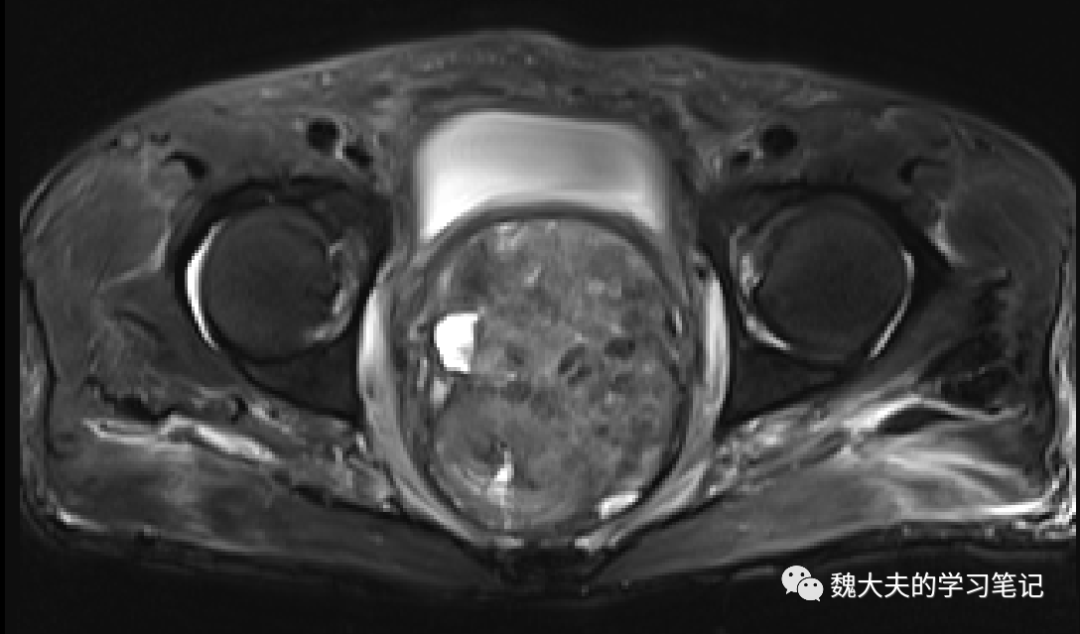

术前 MR检查见直肠巨大占位

图片